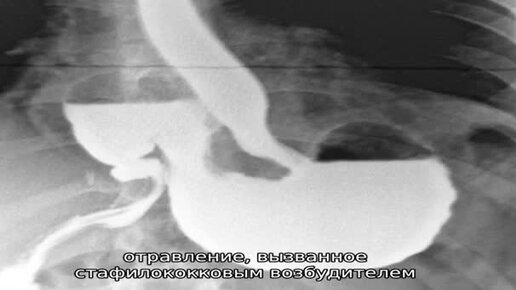

Температура и тошнота_ причины и лечение - медицинские советы, лечение